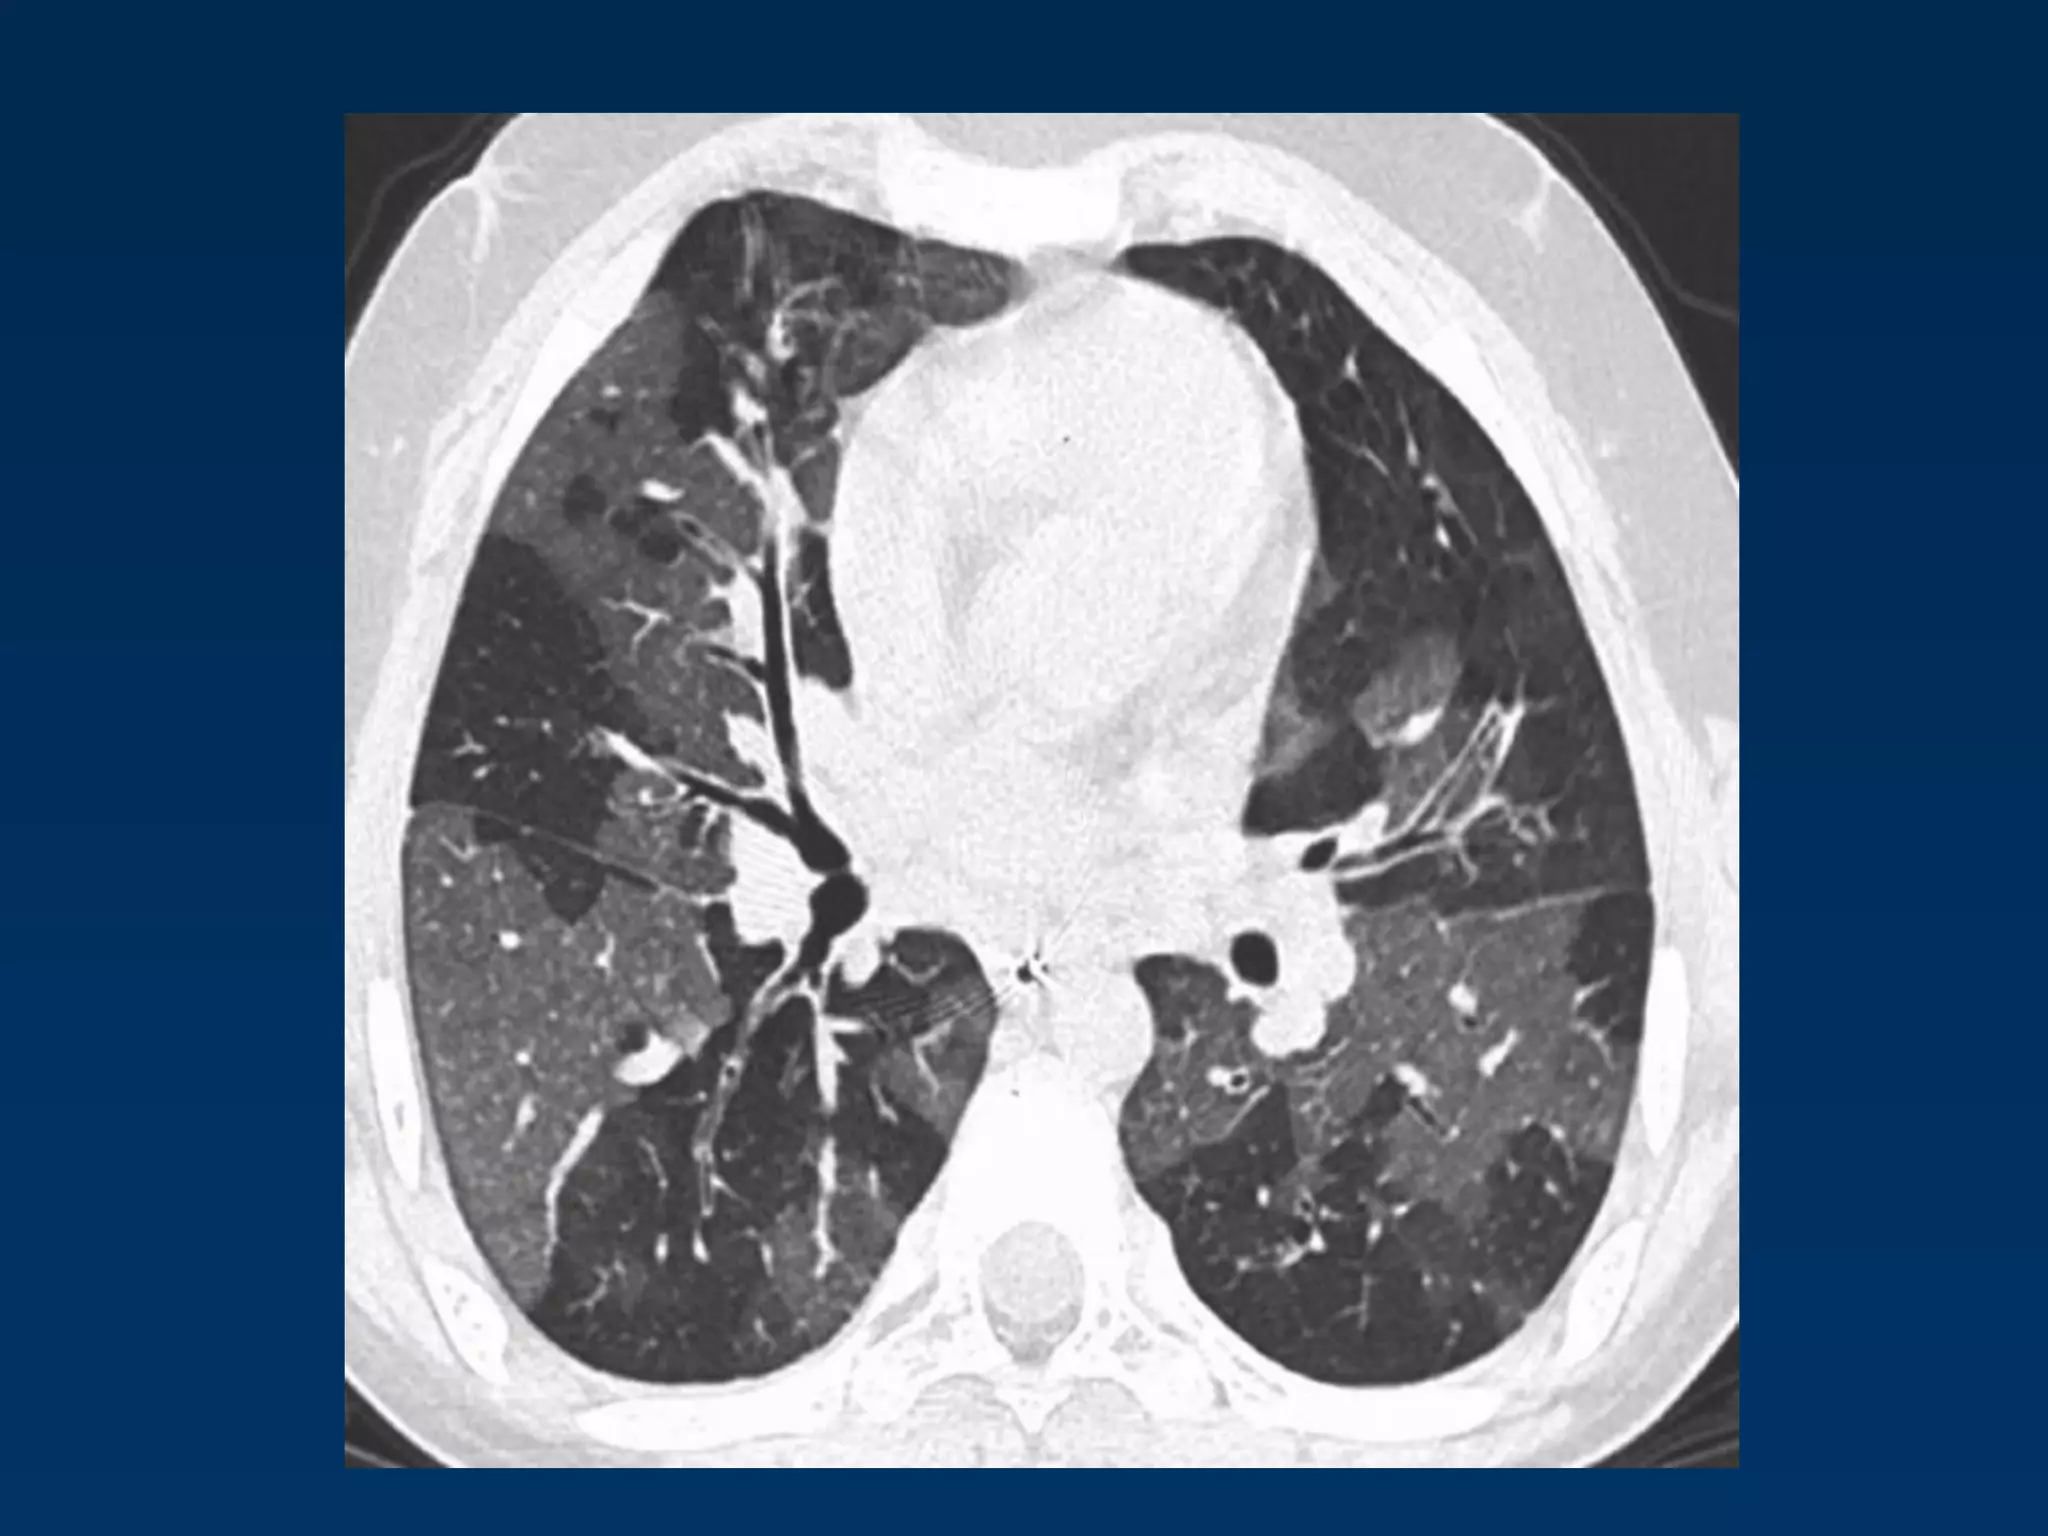

Left Lower Lobe Atelectasis

•

Inhomogeneous cardiac density

Left hilum pulled down

Non-visualization of left diaphragm

Triangular retrocardiac atelectatic LLL